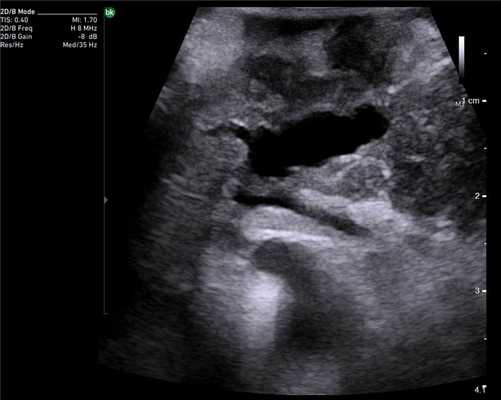

Особенностью проведения интраоперационного ультразвукового исследования у пациентов с первичным поражением печени является то, что гепатоцеллюлярный рак часто развивается на фоне цирроза печени. Следовательно, если опухоль локализуется в толще паренхимы, а так же имеет не большие размеры, пальпаторно определить ее границы крайне затруднительно. Таким образом, задачи установленные перед интраоперационной ультразвуковой томографией были несколько иными, а именно: определение границ опухоли, разметка зоны резекции, определение связи с магистральными сосудами (рис. 2 а,б).

Рис. 2. Метастатические очаги (стрелки) в печени на фоне цирроза.

Клинический пример N3. Пациент Ш. находился на лечении в ГУ РОНЦ РАМН с диагнозом гепатоцеллюлярный рак. При проведении стандартного ультразвукового исследования в правой доле печени было выявлено образование, занимающее практически всю правую долю, с четкими, неровными контурами. На операции пальпаторно определить границу опухоли и неизмененной ткани не представлялось возможным. При проведении интраоперационного ультразвукового исследования была обозначена граница опухолевого образования и неизмененной паренхимы и соотношение этого образования с сосудами печени.